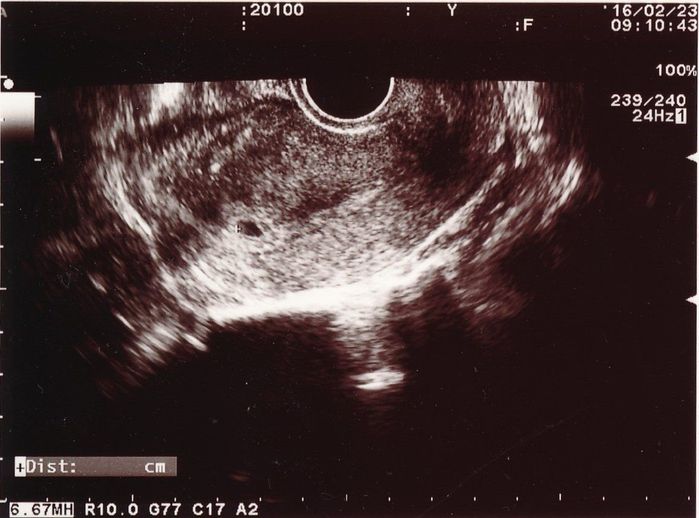

<妊娠初期ごろ>妊娠の確定は高い流産リスクとの闘いの始まり

妊娠5週目のエコー写真

味覚の変化が気になって妊娠検査薬で調べたところ、陽性反応が出たため、翌日に早速、産婦人科へ行きました。これが最初に撮ったエコー写真です。中央左に見える黒い楕円が胎嚢ですが、妊娠に気づくのが早かったようで、この時点では「妊娠の兆候が見られる」とだけ言われ、確定は翌週に持ち越されました。